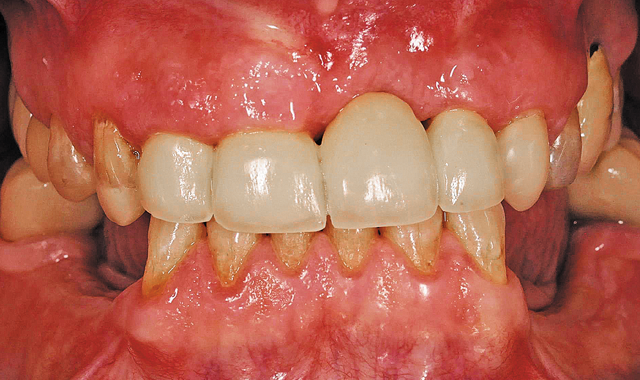

Four-unit anterior bridge design.

02 The doctor first created a four-unit anterior bridge chairside for the patient to establish an initial bite (Fig. 2).